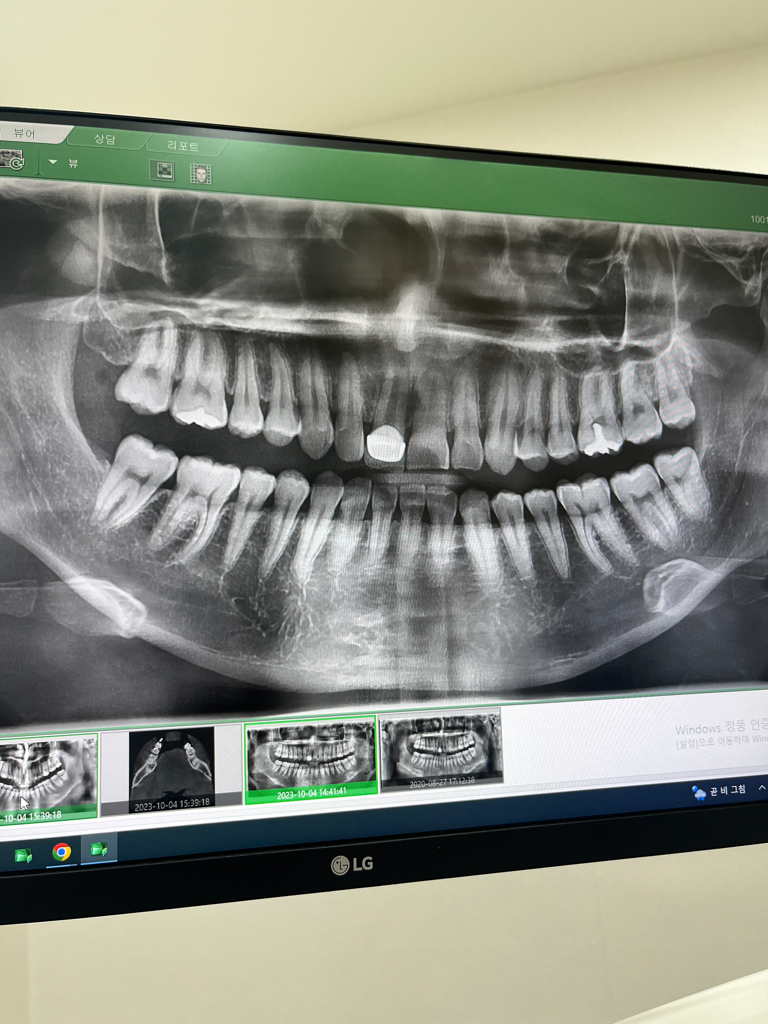

1. 치아 뿌리끝 염증은 정확한 판단을 위해서는 치근단방사선사진(작은방사선사진)이 필요합니다

2. 외상 당시 부러진 정도가 컸다면 신경이 영향을 받았을 수 있습니다. 외상 직후에는 별 증상이 없다가도 시간이 지나면 치아가 변색되면서 치아신경(치수)이 괴사될 수 있습니다. 이렇게 때문에 외상 치아는 상황에 따라 바로 크라운으로 씌우거니 치료를 진행하지는 않고 조금 지켜보는 케이스도 있습니다.

3. 이미 치아 뿌리끝 염증이 잡힐 정도면 치수는 괴사되었을 것이기 때문에 별다른 통증은 없으나 염증이 계속 진행되어 잇몸뼈를 녹이기 때문에 처치(발치, 잇몸치료, 임플란트 또는 브릿지 치료)가 필요합니다.

4. 뿌리끝 염증의 크기나 상태에 따라 다르지만 발치 전 신경치료를 시도해볼 순 있습니다. 현재 크라운만 되어 있고 신경치료는 안되어 있는데 크라운을 뜯고(다시 쓰긴 힘듭니다) 신경치료해서 뿌리끝 염증을 줄이는 시도를 해볼 수는 있습니다

상황에 따라서 크라운을 뜯지 않고 그 위에 구멍을 뚫어 하기도 하지만 시야확보의 어려움 등은 있어 시도를 꺼리는 경우도 있습니다

치아뿌리끝에 염증이 생긴 것을 치근단 농양이라고 합니다. 치근단 농양이 생긴 치아는 살리기 힘든 경우가 많습니다. 그러나 치근단 농양을 수술적 방법으로 치료할 수도 있습니다. 다른 치과에서 다시 상담 받는 것도 한가지 방법입니다.